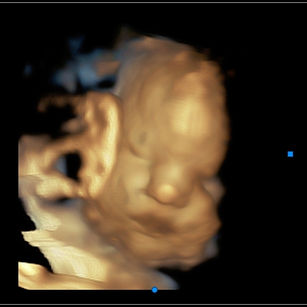

Skin: Now smooth, soft, and pink; most of the protective vernix caseosa (the creamy coating) is fading, though some may still be present at birth.

Eyes: Babies can open and close their eyes and even respond to changes in light.

Grip & reflexes: Strong grasp reflex is present, and rooting and sucking reflexes are well established for feeding.

Most babies are now head down (cephalic position).